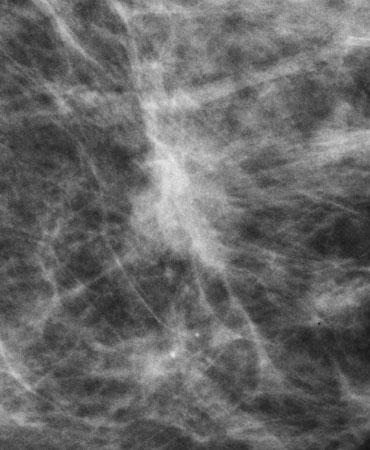

digital mammogram digital tomosynthesis

Invasive Ductal Carcinoma on digital mammogram (above left) and digital tomosynthesis (above right). Digital tomosynthesis shows clear presence of a spiculated mass.